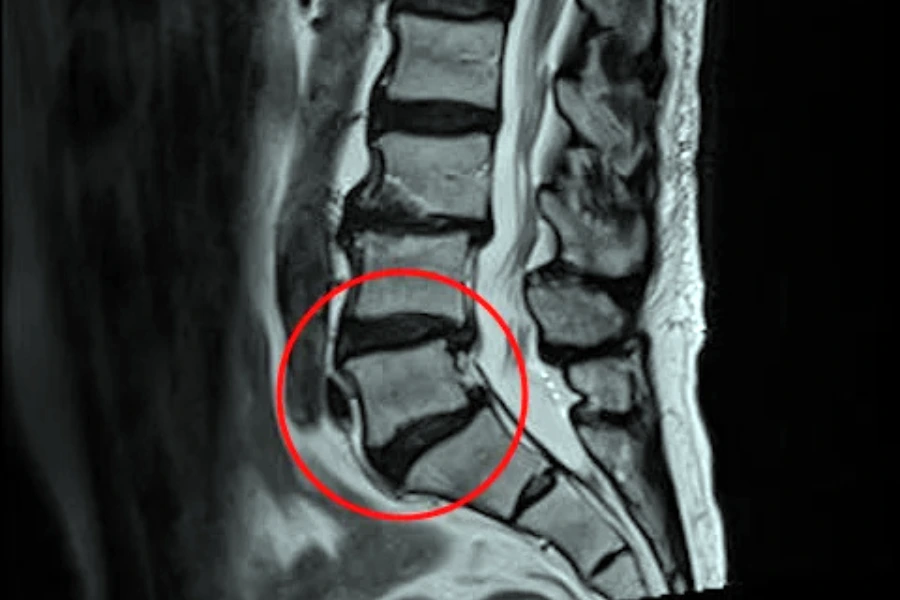

МРТ хребта

Найціннішу інформацію дає магнітно-резонансна томографія (найчастіше призначається МРТ шийного відділу або МРТ поперекового відділу хребта), оскільки вона дозволяє оцінити не лише стан тіл хребців та наявність остеофітів, а й зміни в міжхребцевих дисках, суглобах, зв’язках і нервових структурах. МРТ показує ступінь дегенерації дисків, наявність протрузій і гриж, ознаки запалення або набряку навколишніх тканин, а також дозволяє визначити, чи впливають кісткові розростання на нервові корінці або спинний мозок. Це дослідження є незамінним для диференціації спондильозу від остеохондрозу, адже дає змогу побачити, які зміни є первинними — з боку дисків чи з боку кісткових структур.

КТ хребта

Комп’ютерна томографія доповнює діагностичну картину, оскільки вона найкраще відображає кісткові елементи. На КТ добре видно форму, розміри та напрямок остеофітів, ступінь деформації тіл хребців та можливе звуження міжхребцевих отворів. У випадках, коли виявлений деформуючий спондильоз, КТ дозволяє точно оцінити, наскільки кісткові вирости зменшують просвіт хребетного каналу або створюють компресію нервових структур. Це особливо важливо перед плануванням оперативного втручання.

Порада від нейрохірурга Наталії Скіжа

Застосування МРТ та КТ у комплексі дає максимально повну картину стану хребта, дозволяючи не лише підтвердити діагноз, але й визначити стадію процесу, виявити супутні патології та оцінити ризик прогресування дегенеративних змін. Саме поєднання цих методів забезпечує найвищу точність діагностики та дає змогу підібрати оптимальну тактику лікування для кожного пацієнта окремо.